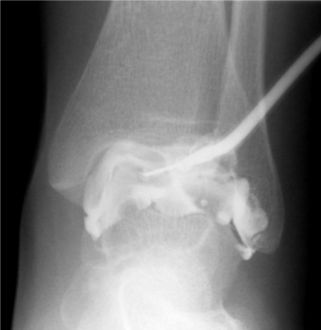

Infiltration d'une bursite calcanéenne sous contrôle échographique image 1

Images 2, 3 et 4 aiguille en place dans la zone hypodense (burste) sous deux incidences orthogonales